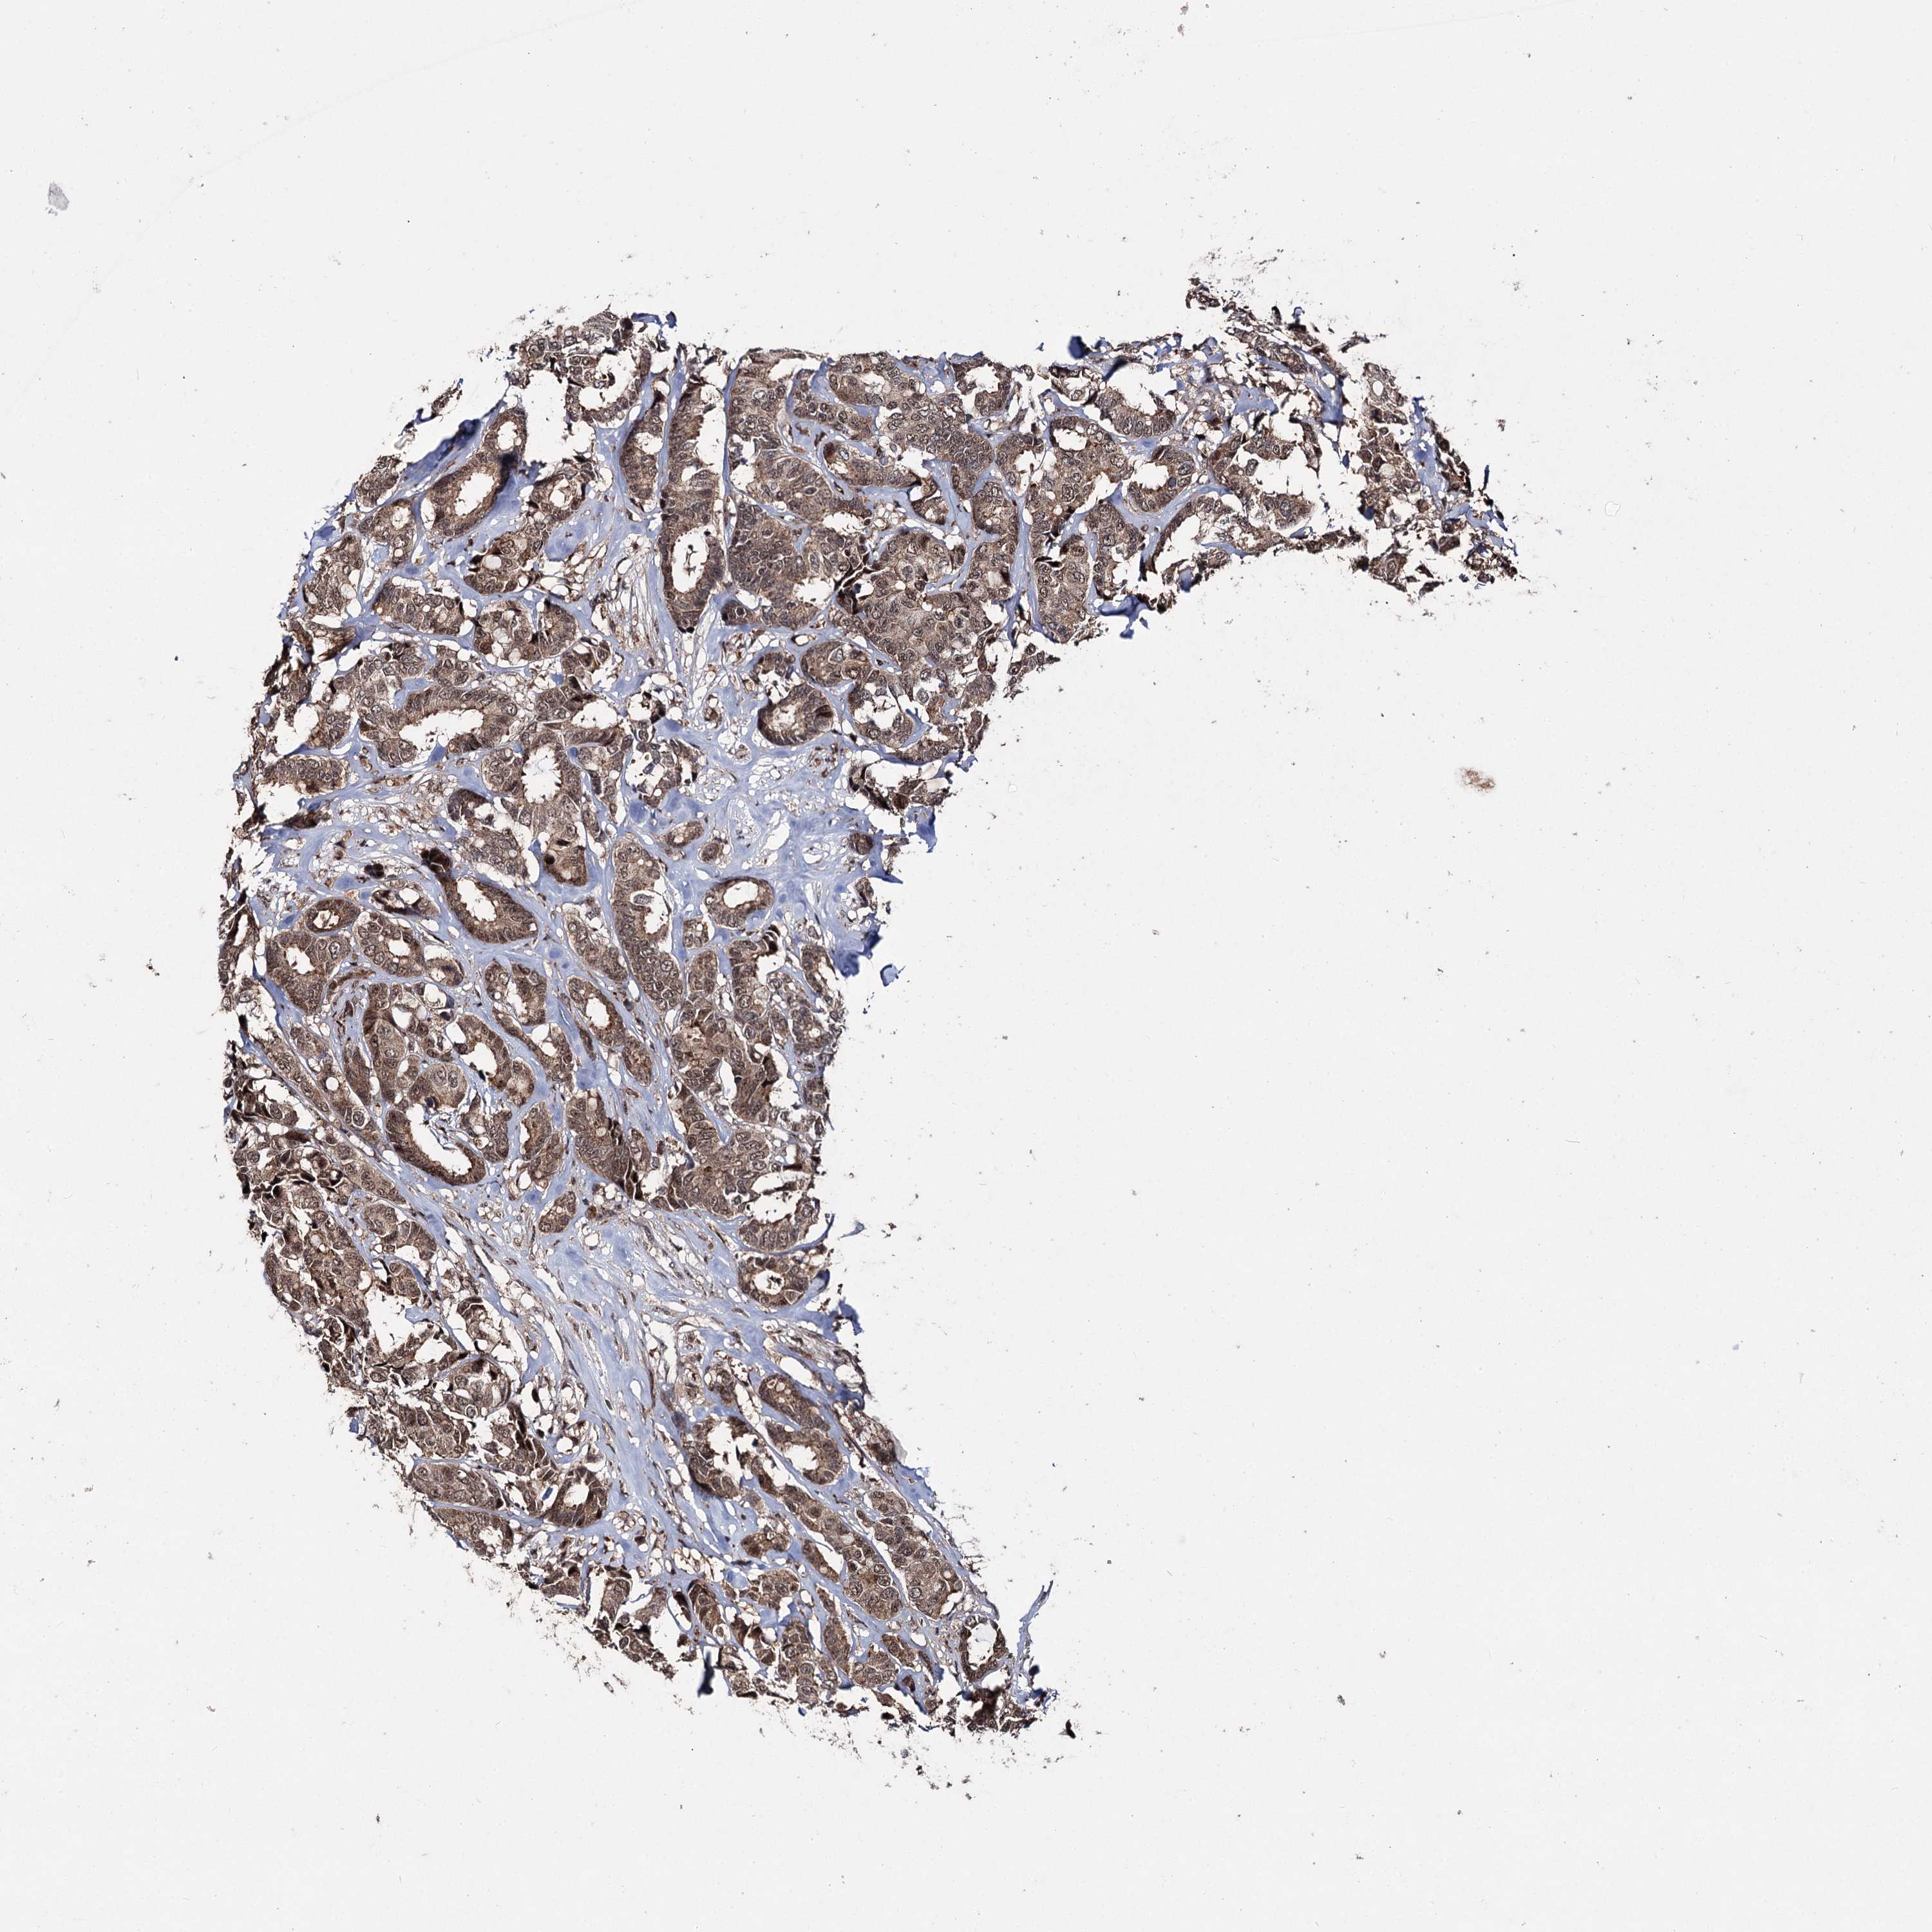

BRCA TCGA BRCA VALIDATION PROTEIN EXPRESSION

ANTIBODIES

AND

VALIDATION